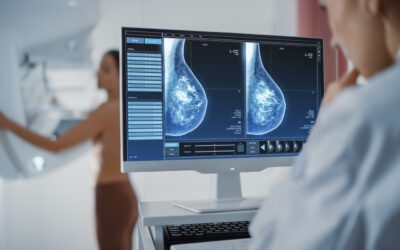

Doctors Fearing COVID-19 Vaccines Are Messing With Mammograms

It has taken about a year of waiting, but now COVID-19 vaccinated women are going to get their mammograms in very large numbers. They are flocking...

COVID-19 Vaccines Confusing Many Mammogram Patients & Results

Hollywood Diagnosticss Center has noticed something interesting that has come about from the results of the COVID-19 vaccines being given out to the...